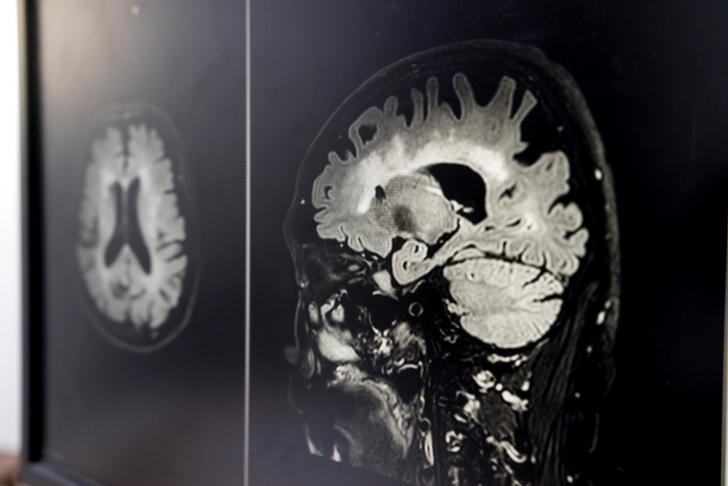

Vascular dementia is the second most common form of dementia, affecting millions of people worldwide. It occurs when blood flow to the brain is reduced, depriving brain cells of the oxygen and nutrients they need to function properly. This article will explore the causes, early signs, and symptoms of vascular dementia to provide a comprehensive understanding for laypeople.